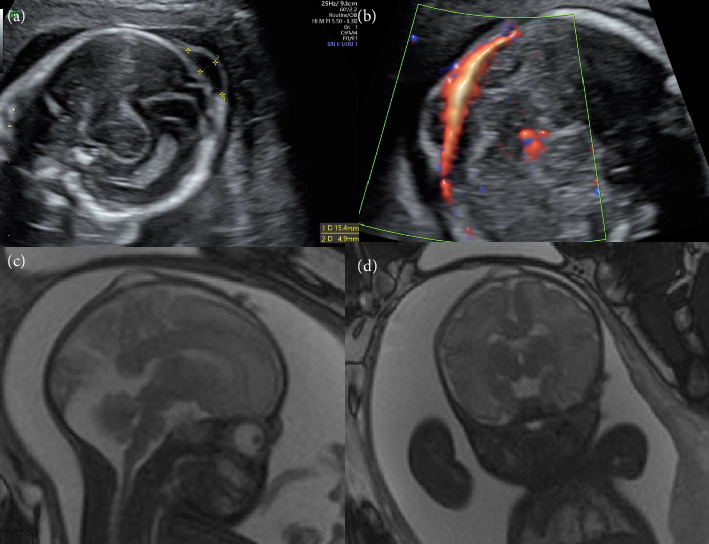

Determining the differential diagnosis of small scalp cysts identified on a fetus is difficult. In particular, many physicians have difficulty differentiating small meningoceles from small scalp cysts during the prenatal period. Volume contrast imaging increases contrast between tissues, thereby allowing an enhanced view of target structures. A 15 × 5 mm scalp cyst was identified on a fetus during a prenatal ultrasonography examination performed at 20 weeks of gestation. The cyst was not connected to the blood flow, and did not include the tissue of the brain parenchyma. Ventriculomegaly and other structural abnormalities were not observed. Based on these findings, we suspected a sinus pericranii or fetal epidermal cyst. The size of the fetal scalp cyst was stable, and the growth of the fetus remained normal until birth. The diagnosis of a small meningocele was confirmed postnatally, based on the results of a magnetic resonance imaging examination. Postnatal evaluation of offline volume contrast imaging of prenatal three-dimensional ultrasound data at 22 weeks of gestation revealed a skull bone defect beneath the cyst. Volume contrast imaging can facilitate the prenatal diagnosis of small meningoceles by detecting bone defects on the fetal head.

Abstract Image